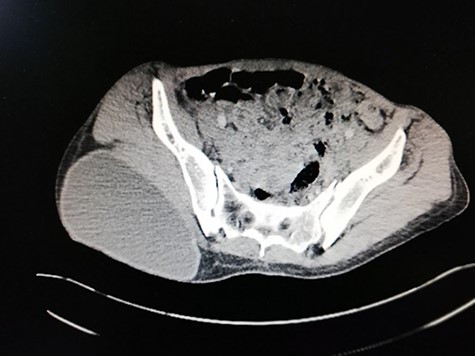

Abdominal ultrasound delineated multiple cystic lesions in the liver and the spleen. Computed tomography (CT) scan showed up to six rounded homogenous low-density cysts in both lobes of the liver, ranged from 0.15 to 0.17 m, and one large cyst in the spleen, containing multiple peripheral small vesicular cysts (Fig. 1). CT scan showed a 0.03 × 0.07 m cyst in the upper mediastinum, adjacent to the aortic arch (Fig. 2A); two rounded well-defined homogenous cysts in the lower lobe of the left lung, measured 0.17 × 0.17 m, and in both breasts (Fig. 2B and C) and a single large 0.2 × 0.13 m oval homogenous cyst above the right gluteal muscles (Fig. 3).

Pelvic CT scan reveals: a large oval homogenous cyst, above the right gluteal muscles, measuring 0.2 × 0.13 m.